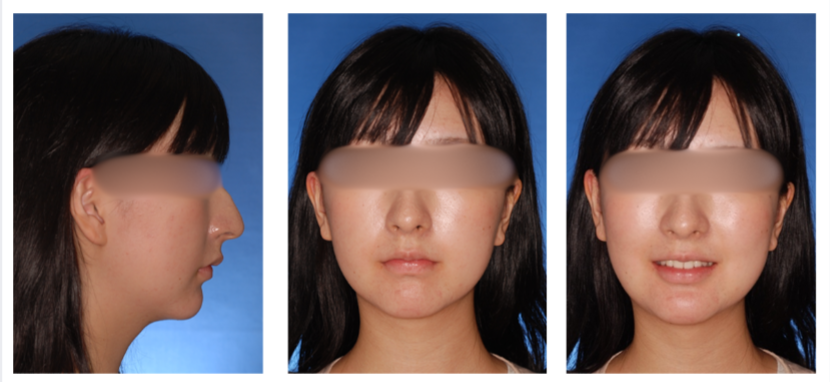

外科症例(反対咬合)の症例

初診時

治療終了時

治療終了から3年経過時

(保定開始から3年経過時)

初診

治療終了時

治療終了後から3年経過時

(保定開始時から3年経過時)

| 年齢・性別 |

20代 女性 |

| 主訴 |

咬み合わせが逆なのが気になる。 |

| 治療について |

骨格的な問題が大きいことから外科的矯正治療としました。 |

| 治療期間 |

2年9ヶ月 |

| 治療費用 |

累計約550,000円(保険適用の治療になります。 手術費用も含んだ総額です。) |

| 治療に用いた主な装置 |

マルチブラケット装置(表側の装置)、歯科矯正用アンカースクリュー、パラタルレバーアームシステム |

| 抜歯部位 |

上顎左側第二小臼歯、右側第一小臼歯、両側第二大臼歯、下顎両側第三大臼歯を抜歯 |

| 通院回数 | 26回 |